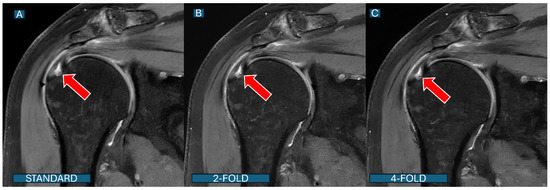

Figure 5. A partial articular-sided supraspinatus tear: a comparison across protocols. Coronal PD fat-saturated images from a 68-year-old patient with shoulder pain demonstrate a partial tear of the supraspinatus tendon (red arrows). The tear is clearly visible with similar diagnostic confidence in all three protocols: (A): the standard protocol; (B): the DL2 protocol; and (C): the DL4 protocol. Note that despite acceleration, both DL protocols maintain excellent visualization of the complete tear morphology.